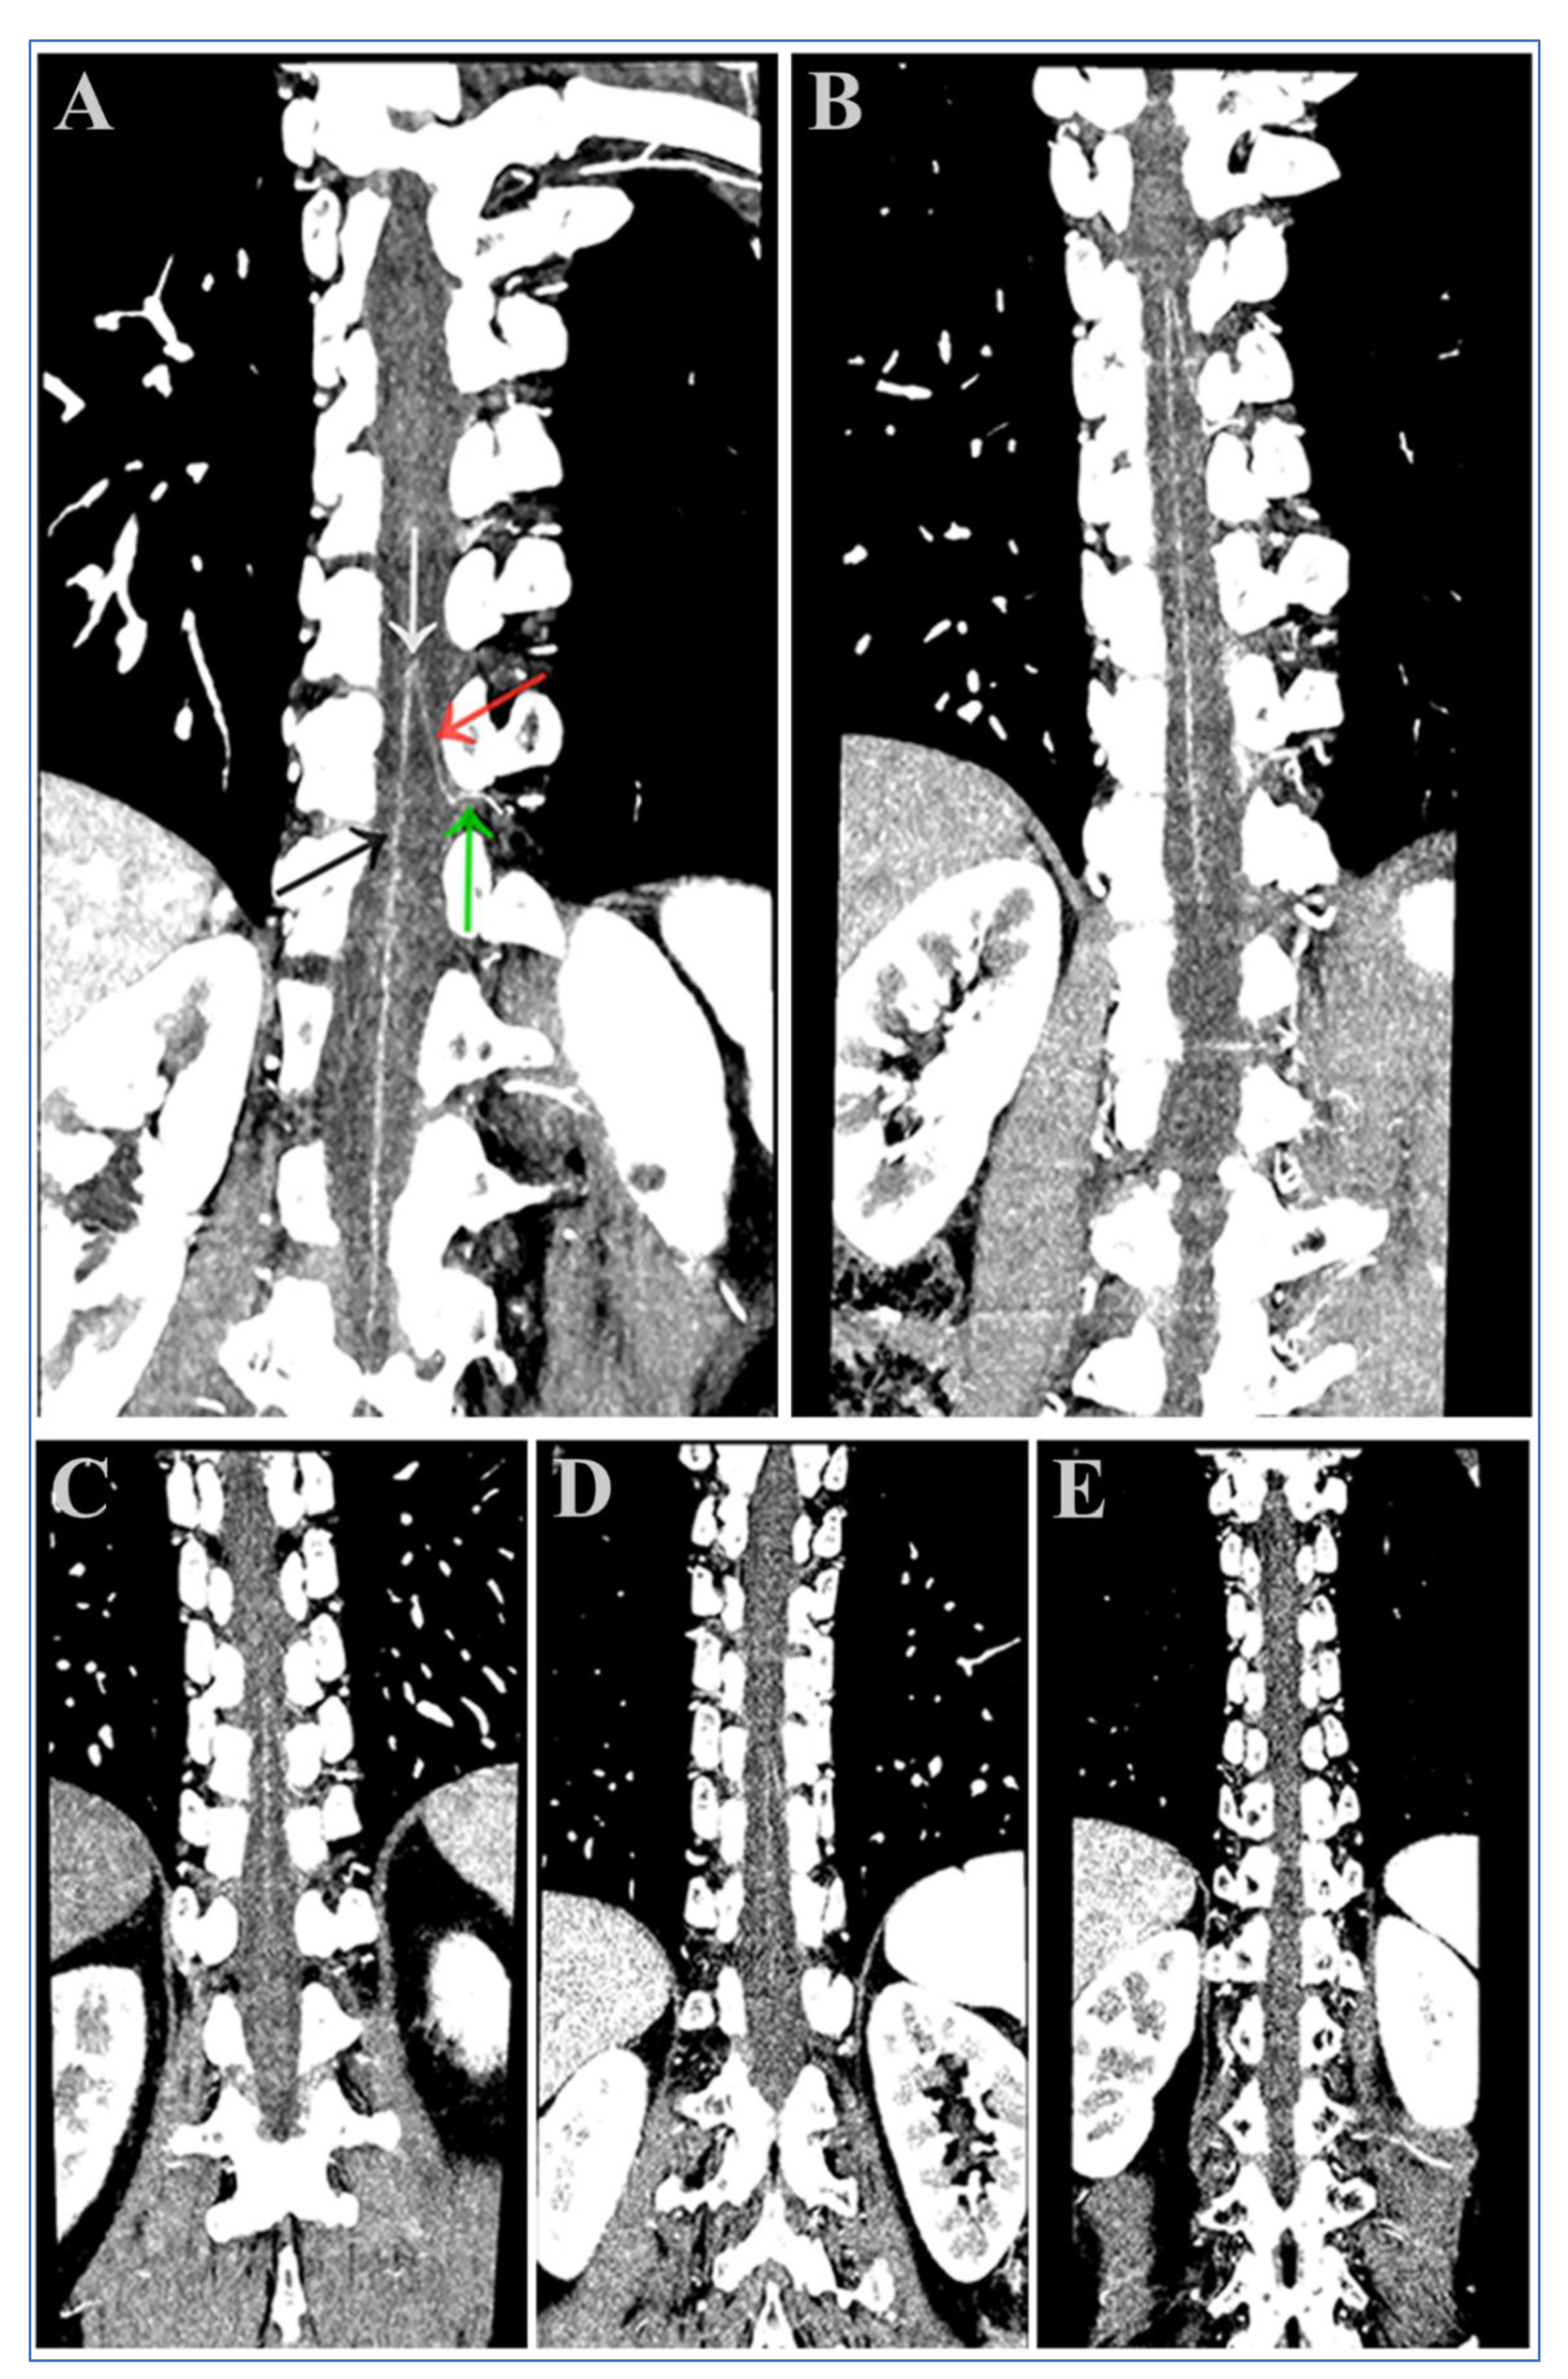

3.4. Visual Analysis of the AKA